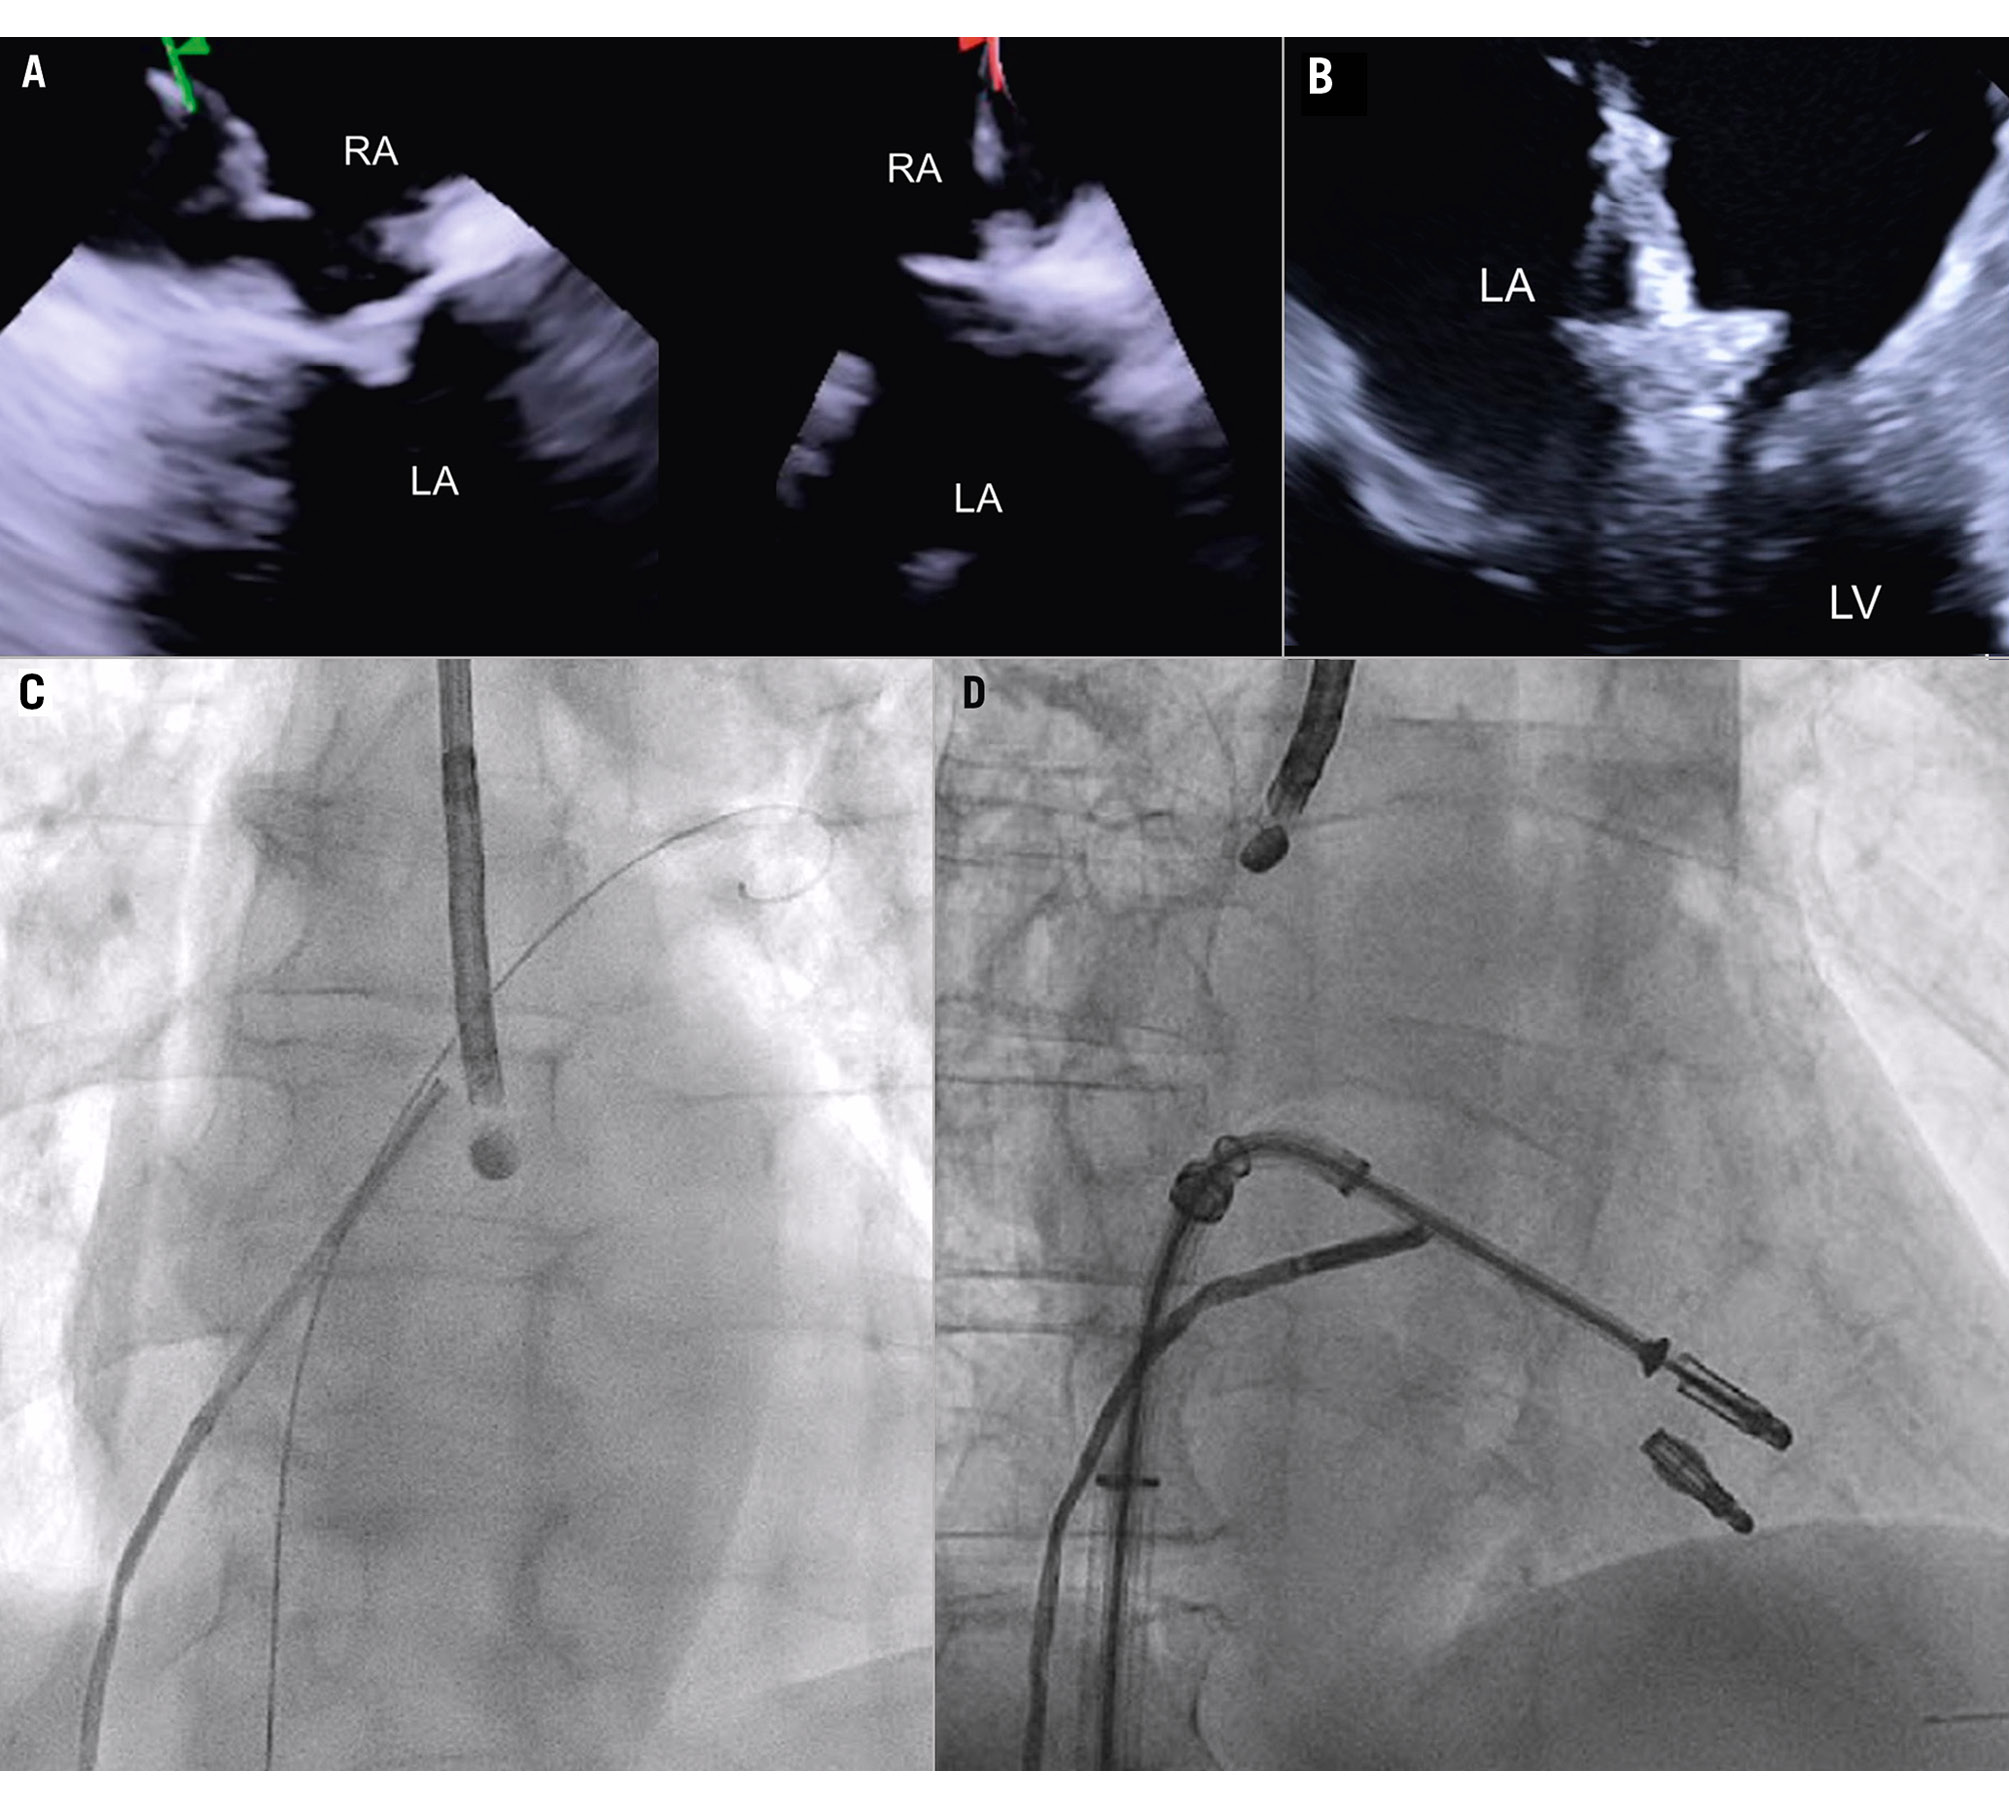

Imaging the MV with ICE implies crossing the interatrial septum and positioning the imaging catheter in the left atrium, a step that can be technically challenging. The TSP is performed using simultaneous biplane imaging with the ICE catheter positioned in the middle of the right atrium and retroflexed towards the septum (Figure 7A). A preshaped stiff wire is carefully positioned into the upper left pulmonary vein under fluoroscopic and ICE guidance (Figure 7B). Predilatation of the septum is required to facilitate the advancement of the ICE catheter into the LA while tracking the trajectory of the wire (Figure 7B). This can be done either by advancing and retracting the TEER-guiding catheter or through preparatory balloon septostomy using a 12-14 mm over-the-wire percutaneous transluminal angioplasty balloon. Once the ICE catheter has been placed successfully into the left atrium, it is followed by the guiding sheath, and the implant itself is then advanced towards the diseased MV (Figure 7C). While the ICE catheter usually follows the curve of the delivery system, a position below it (Figure 7D) or the use of the right and left deflexion knob minimises shadowing artefacts and avoids direct interaction with the TEER device or any other catheter used for the intervention. The key advantage of RT 3D catheters is the ability to produce MPR that facilitates simultaneous optimisation of the trajectory and orientation in several planes and on the 3D view from the atrium (Figure 8, Figure 9A-Figure 9B-Figure 9C, Moving image 9-Moving image 10-Moving image 11). At the end of the procedure, closure of the interatrial septum should be considered (Figure 9D), since the defect is usually larger than after conventional TEER due to the manipulation of two catheters through the same access. Closure can be easily guided with the ICE catheter back to the right atrium (Figure 9E). Mini-TOE or a paediatric probe (without 3D capabilities), as well as transthoracic echocardiography26 are additional confirmatory imaging modalities that can be used in combination with ICE (Figure 9F).

Figure 7. ICE-guided transseptal puncture. A) Transseptal puncture using biplanar imaging with the ICE catheter retroflexed in the middle of the RA. Needle tenting is seen simultaneously in two dimensions. B) Position of the delivery catheter over the diseased mitral valve. C) After wire placement and septum predilatation, the ICE catheter is moved into the LA following the trajectory of the stiff wire. A paediatric TOE probe without 3D capacity is inserted into the oesophagus. D) Position of the ICE catheter below the TEER system to avoid shadowing artefacts. 3D: three-dimensional; ICE: intracardiac echocardiography; LA: left atrium; RA: right atrium; TEER: transcatheter edge-to-edge repair